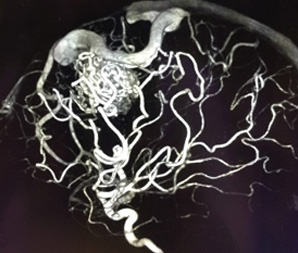

脳動静脈奇形とは、脳にできた異常な血管のかたまり(ナイダス)のことをいいます。通常、脳を栄養する血液は、動脈→毛細血管→静脈の順に流れ、毛細血管から脳へ栄養や酸素を送っています。これに対して、脳動静脈奇形は脳内の動脈と静脈が血管のかたまりであるナイダスで直接つながっており、この中を大量の血液が勢いよく流れています。

1 開頭ナイダス摘出術

- 実際に開頭して、異常血管であるナイダスを摘出する手術です。

- 侵襲の高い治療になりますが、利点として根治性が高い点が挙げられます。